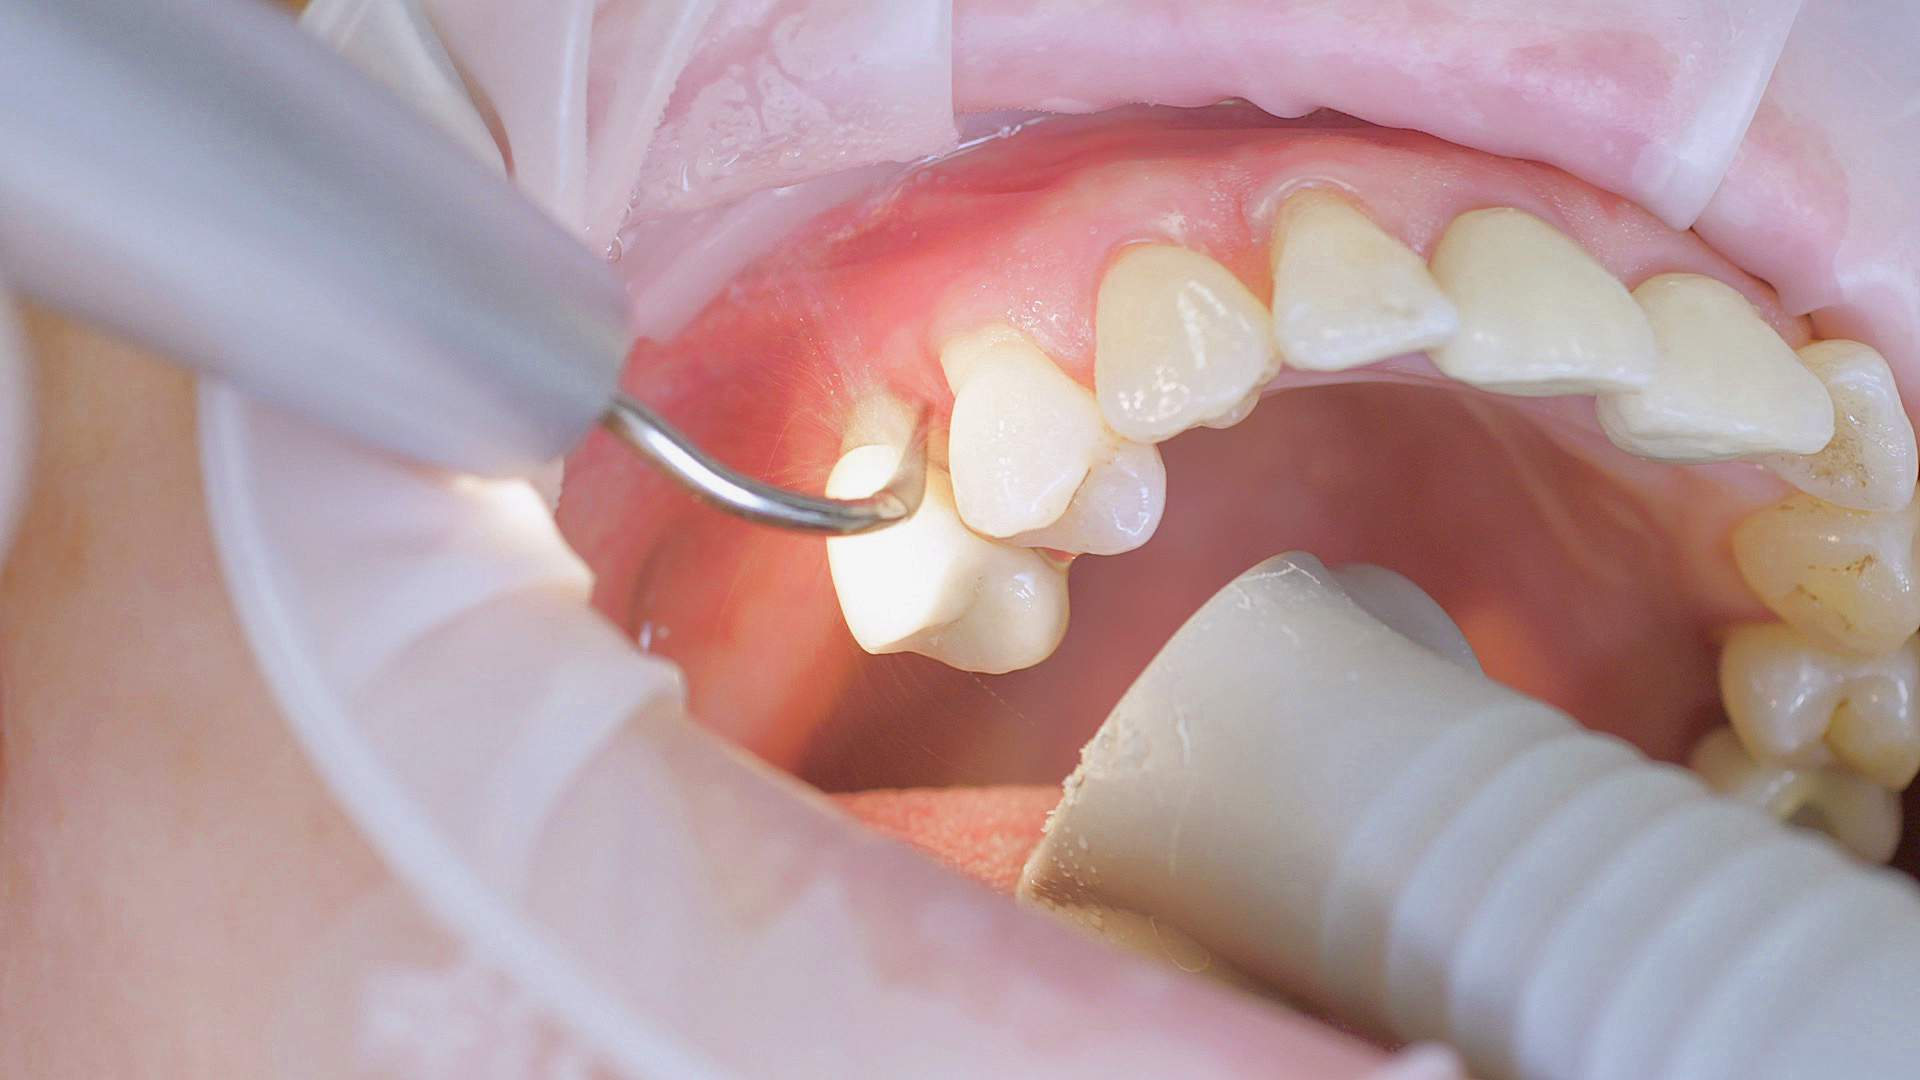

Removal of subgingival coatings (debridement) is carried out using sonic or ultrasonic devices and special periodontal tips as initial periodontal treatment (Fig. 3). Manual instruments can also be used. Further surgical and/or regenerative measures may be necessary, depending on the situation.

In the periodontal aftercare subsequent to implantation, soft (biofilm) and hard coatings are regularly professionally and mechanically removed.[16, 17] In the subgingival and supragingival areas, ultrasonic devices are generally used for this (Fig. 4), in combination with manual instruments where necessary. Alternatively, subgingival air polishing can be used in combination with periodontal attachments and powders.[18]